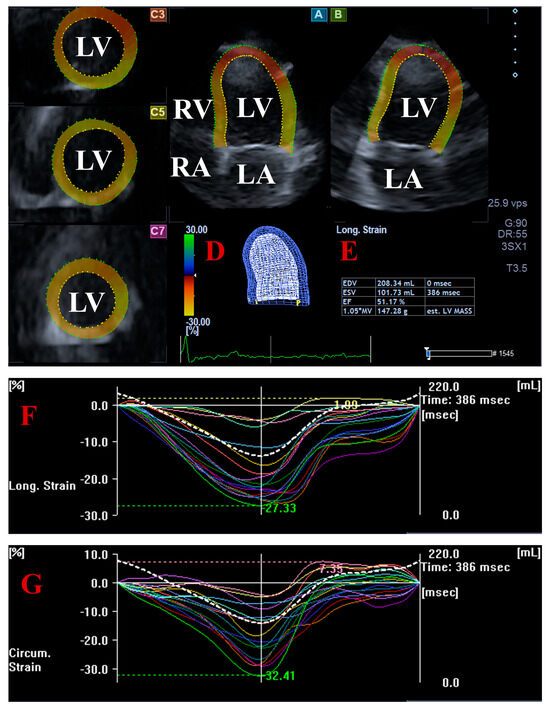

Background: Acromegaly, typically caused by growth hormone (GH)-secreting pituitary adenomas, leads to chronic GH and insulin-like growth factor-1 overproduction, resulting in significant cardiovascular complications, including left ventricular (LV) hypertrophy, myocardial fibrosis, diastolic/systolic LV dysfunction, and frequent valvular disease. Although aortic root dilation has been documented, the morphology and function of the aortic valve annulus (AVA) and its relationship with LV performance remain unexplored. Methods: The present study comprised a total of 31 patients with acromegaly, from which eight subjects were excluded due to inferior image quality. The remaining group of acromegalics consisted of 23 cases (mean age: 54.3 ± 14.5 years, 6 males). Their results were compared to 31 age- and gender-matched healthy subjects (mean age: 50.0 ± 7.4 years, 9 males). Cardiac assessment involved routine two-dimensional Doppler echocardiography and three-dimensional speckle-tracking echocardiography (3DSTE) to quantify basal regional and global longitudinal strains. Detailed planimetric measurements of AVA dimensions and its spatial displacement, called AVA plane systolic excursion (AAPSE), were also obtained. Results: Among 12 patients with inactive acromegaly, 7 patients (58%) showed larger end-systolic AVA area (AVA-A), while 5 patients (42%) had larger end-diastolic AVA-A. Among the 11 patients with active acromegaly, 3 patients (27%) had larger end-systolic AVA-A and 5 patients (45%) had larger end-diastolic AVA-A, while in 3 patients (27%) end-systolic and end-diastolic AVA-A proved to be equal. All end-systolic and end-diastolic AVA dimensions were tendentiously greater in acromegaly, with more pronounced values seen in the presence of an active disease. AAPSE was reduced both in all acromegaly patients and in those with active disease compared to controls. From LV strains, basal and global LV longitudinal strain (LS) and basal LV circumferential strain (CS) were similar when comparing acromegaly patients and those with active and inactive disorder to controls. However, basal and global LV-LS tended to be reduced, while basal LV-CS tended to be increased. Significantly increased global LV-CS were present in active acromegaly patients compared to inactive acromegaly patients and controls Conclusions: Significant aortic valve annular dilation is present in acromegaly, which is associated with its reduced spatial systolic displacement. Full article

Figure 1